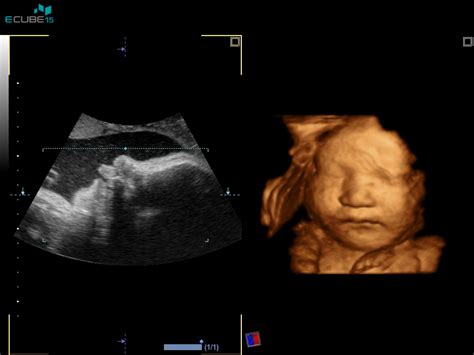

V 70. in 80. letih 20. stoletja se je začela razvijati medicina plodu (fetalna medicina), kar je omogočilo spremljanje rasti plodu v zadnjih desetletjih. Zastoj v rasti plodu torej pomeni, da je ocenjena velikost plodu manjša, kot bi jo pričakovali glede na trajanje nosečnosti. Rast plodu ocenjujemo z ultrazvokom (UZ), pri čemer ultrazvočne meritve vnašamo v rastne krivulje, da tako sledimo njegovi rasti.

Ob ugotovitvi, da plod zaostaja v rasti (včasih je potrebnih več meritev v razmaku od dveh do štirih tednov, da opredelimo zastoj rasti), vedno ocenimo še količino plodovnice, izgled posteljice, telesne strukture plodu (morfologija plodu), pretoke skozi različne žile in zdravstveno stanje nosečnice. Šele na podlagi analize vseh dejavnikov, ki lahko vplivajo na rast plodu, in opažanj se odločimo, kako bomo ukrepali. Včasih odvzamemo vzorec plodovnice, da izključimo kromosomske bolezni plodu, včasih zdravimo nosečnico, iščemo okužbe, včasih se odločimo za takojšen porod ali pa samo za podrobnejše spremljanje rasti plodu. Kako bomo ukrepali, je odvisno od trajanja nosečnosti in spremljajočih ugotovitev; enotnega recepta ni.